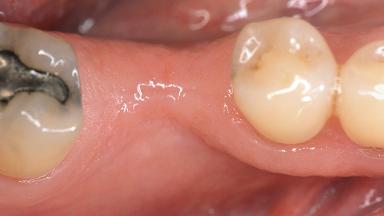

Soft-Tissue Volume Augmentation Using a Connective-Tissue Graft Harvested from the Maxillary Tuberosity

In 1983, a 51-year-old non-smoking patient was referred for the treatment of moderate chronic periodontitis. At the initial examination, 47% of sites exhibited probing depths of 4 to 6 mm. Periodontal therapy consisted of initial periodontal treatment including oral-hygiene instructions and supra- and subgingival debridement, followed by periodontal surgery to eliminate residual pockets.